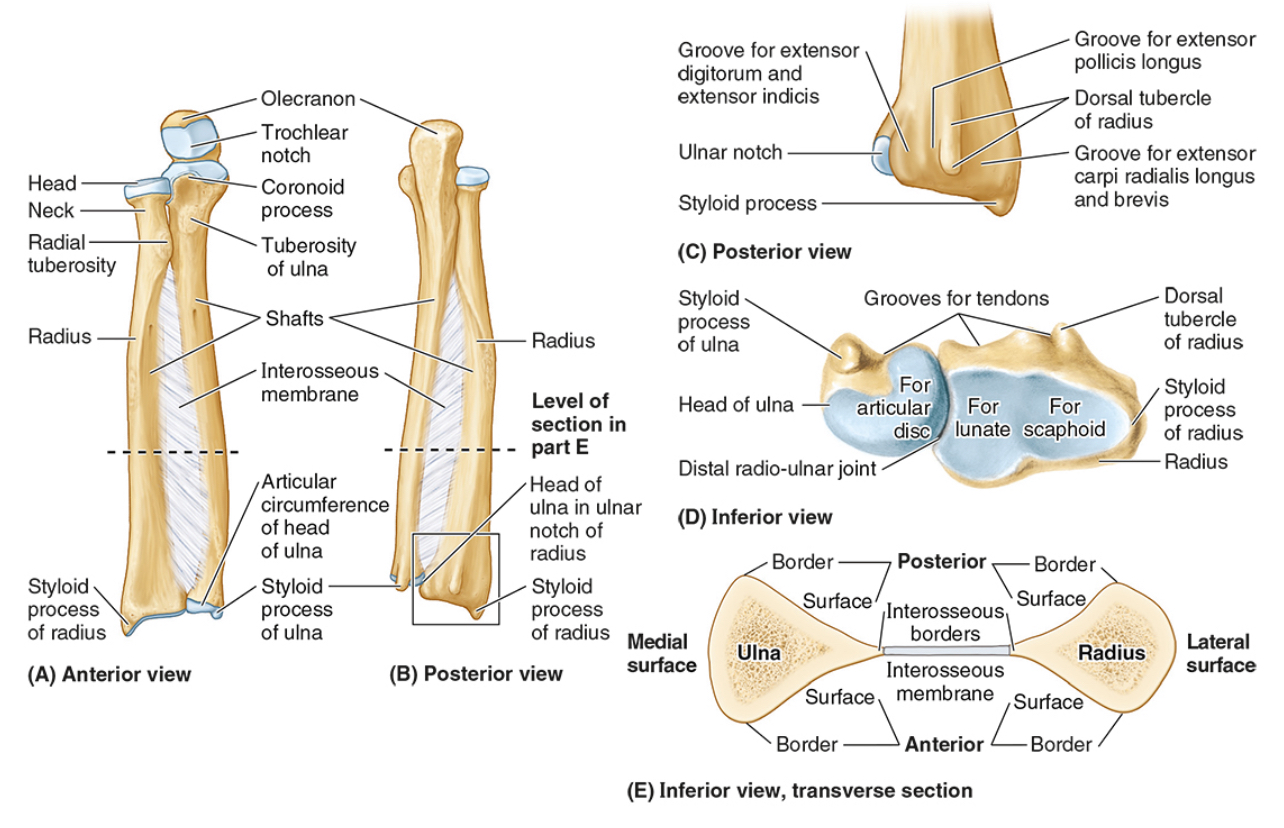

The ______ connects to the carpal bones of the hand at the wrist joint. The _____ widens distally to provide the proximal articular surface of the wrist (remember, the _____ is on thumb side of the wrist!)

(all the blanks are the same word)

Radius

The head of the radius

The neck of the radius

The radial tuberosity

The ulnar notch

The styloid process

The ____ is the medial forearm bone

Ulna

the olecranon (superior)

The coronoid processes (inferior)

The trochlear notch

The tuberosity of the ulna

The radial notch

The head of the ulna

Distal radio-ulnar joint